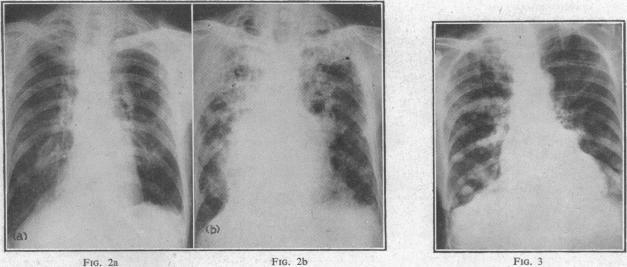

Lung lesions in rheumatoid arthritis.

Br Med J. 1955 Jul 23;2(4933):228-32. doi: 10.1136/bmj.2.4933.228.